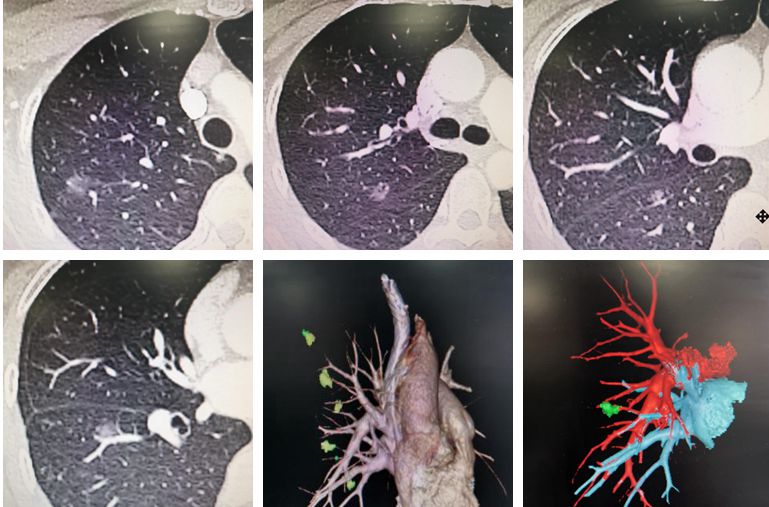

近日,素股 胸外科成功为一例多原发肺癌(multiple primary lung cancers,MPLC)患者实施手术,患者术后恢复良好。患者是一位52岁的女性,因“查体发现双肺多发...